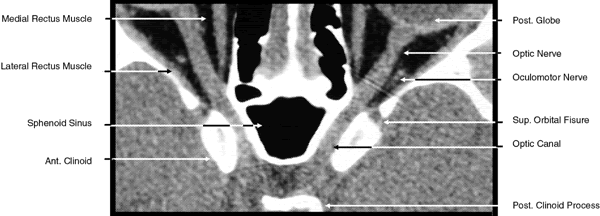

The globe is shown in Figure 12. The orbit and periorbital structures are shown in Figures 13 through 16, and the optic canal is shown in Figures 17 through 26. The cavernous sinus and optic chiasm are shown in Figures 27 and 28, and the posterior visual pathway and cranial nerves are shown in Figures 29 through 33.

Fig. 23. Axial images at the level of midorbit. A. Computed tomography scan. B. T1-weighted magnetic resonance imaging.

Fig. 24. Axial images at the level of superior orbit. A. Computed tomography scan. B. T1-weighted magnetic resonance imaging.

Fig. 25. Axial images at the level of tendon of the superior oblique. A. Computed tomography scan. B. T1-weighted magnetic resonance imaging.